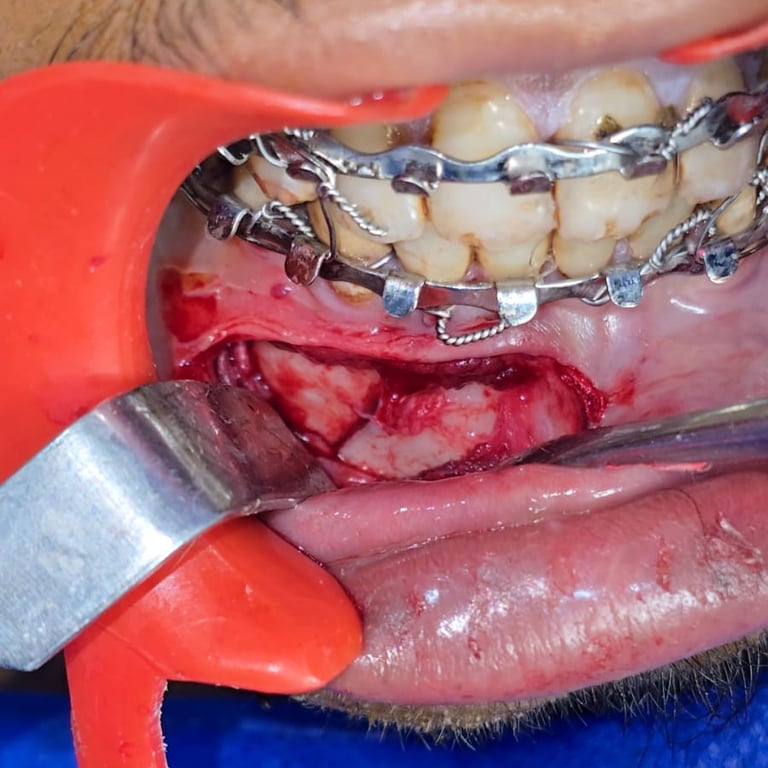

Surgery & Recovery

See how we treated a parasymphysis mandibular fracture in an 18-year-old male using IMF & plating. Scar-free recovery in just 15 days.